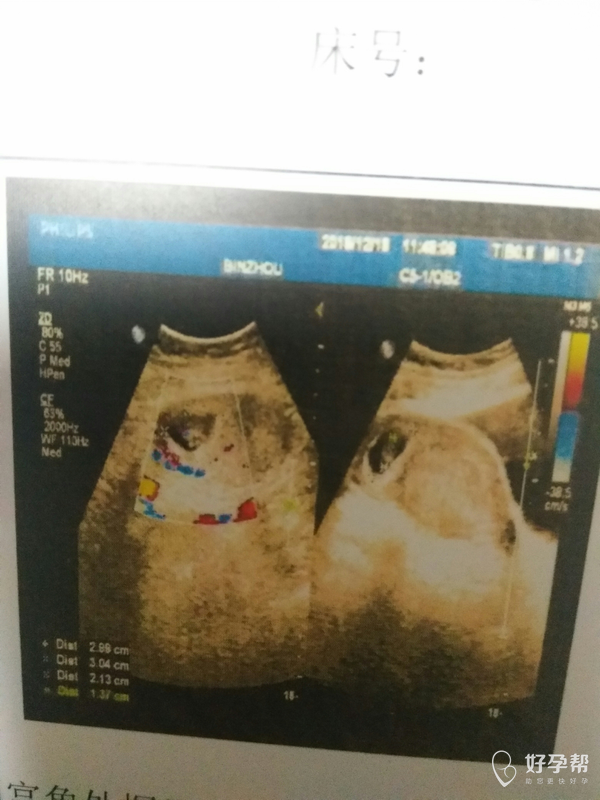

右侧宫角妊娠,想保住孩子,希望大吗?

孕七周B超检查,有,孕囊位于右侧宫角处,过十天再检查孕囊还是在宫角,孕囊距浆膜层的距离还是5㎜。医生让继续观察,有没有可能宝宝自己游回子宫,很担心。很想保住孩子,想知道希望有多大?